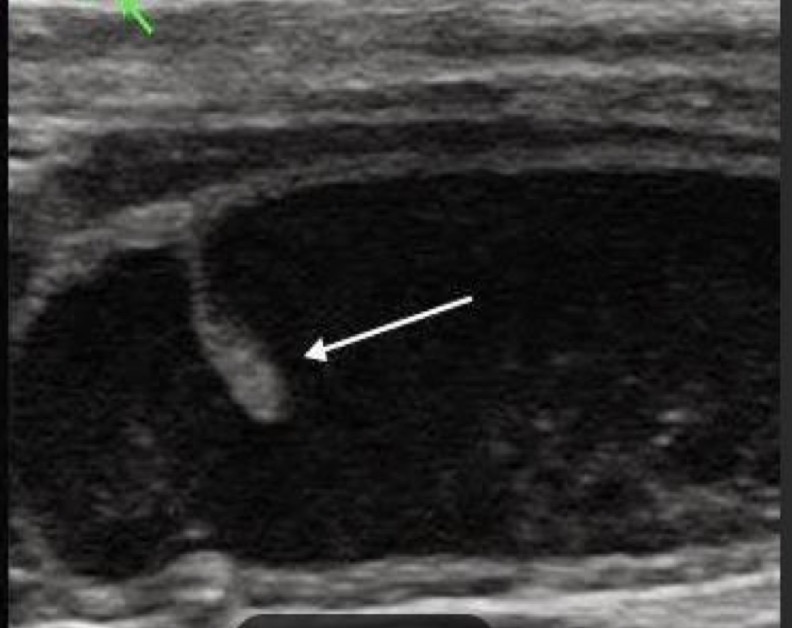

Hydronephrosis

What is this arrow pointing to?